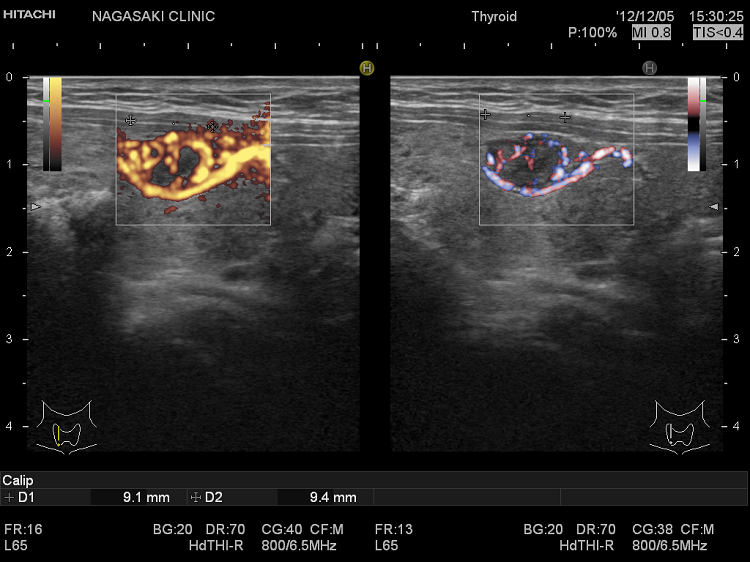

高精細なカラー表示機能「eFlow(イー フロー)」を搭載。通常のカラー表示よりも、血管からのはみ出しが少なく、甲状腺内の微細血流が鮮明に見えます。

詳細は、eFlow(イー フロー;甲状腺の微細血流) をご覧ください。

甲状腺機能亢進症/バセドウ病

甲状腺機能低下症/橋本病の甲状腺内血流増加

甲状腺機能低下症/橋本病でも甲状腺内血流の増加が起こります。橋本病における甲状腺内の血流は、甲状腺機能低下の程度、特に甲状腺刺激ホルモン(TSH)の上昇度と相関します。TSHが血管内皮細胞増殖因子(VEGF)を増加させることが原因と考えられます。甲状腺機能亢進症/バセドウ病のカラードプラ所見に似ていますが、症状が真逆なので鑑別は容易です。